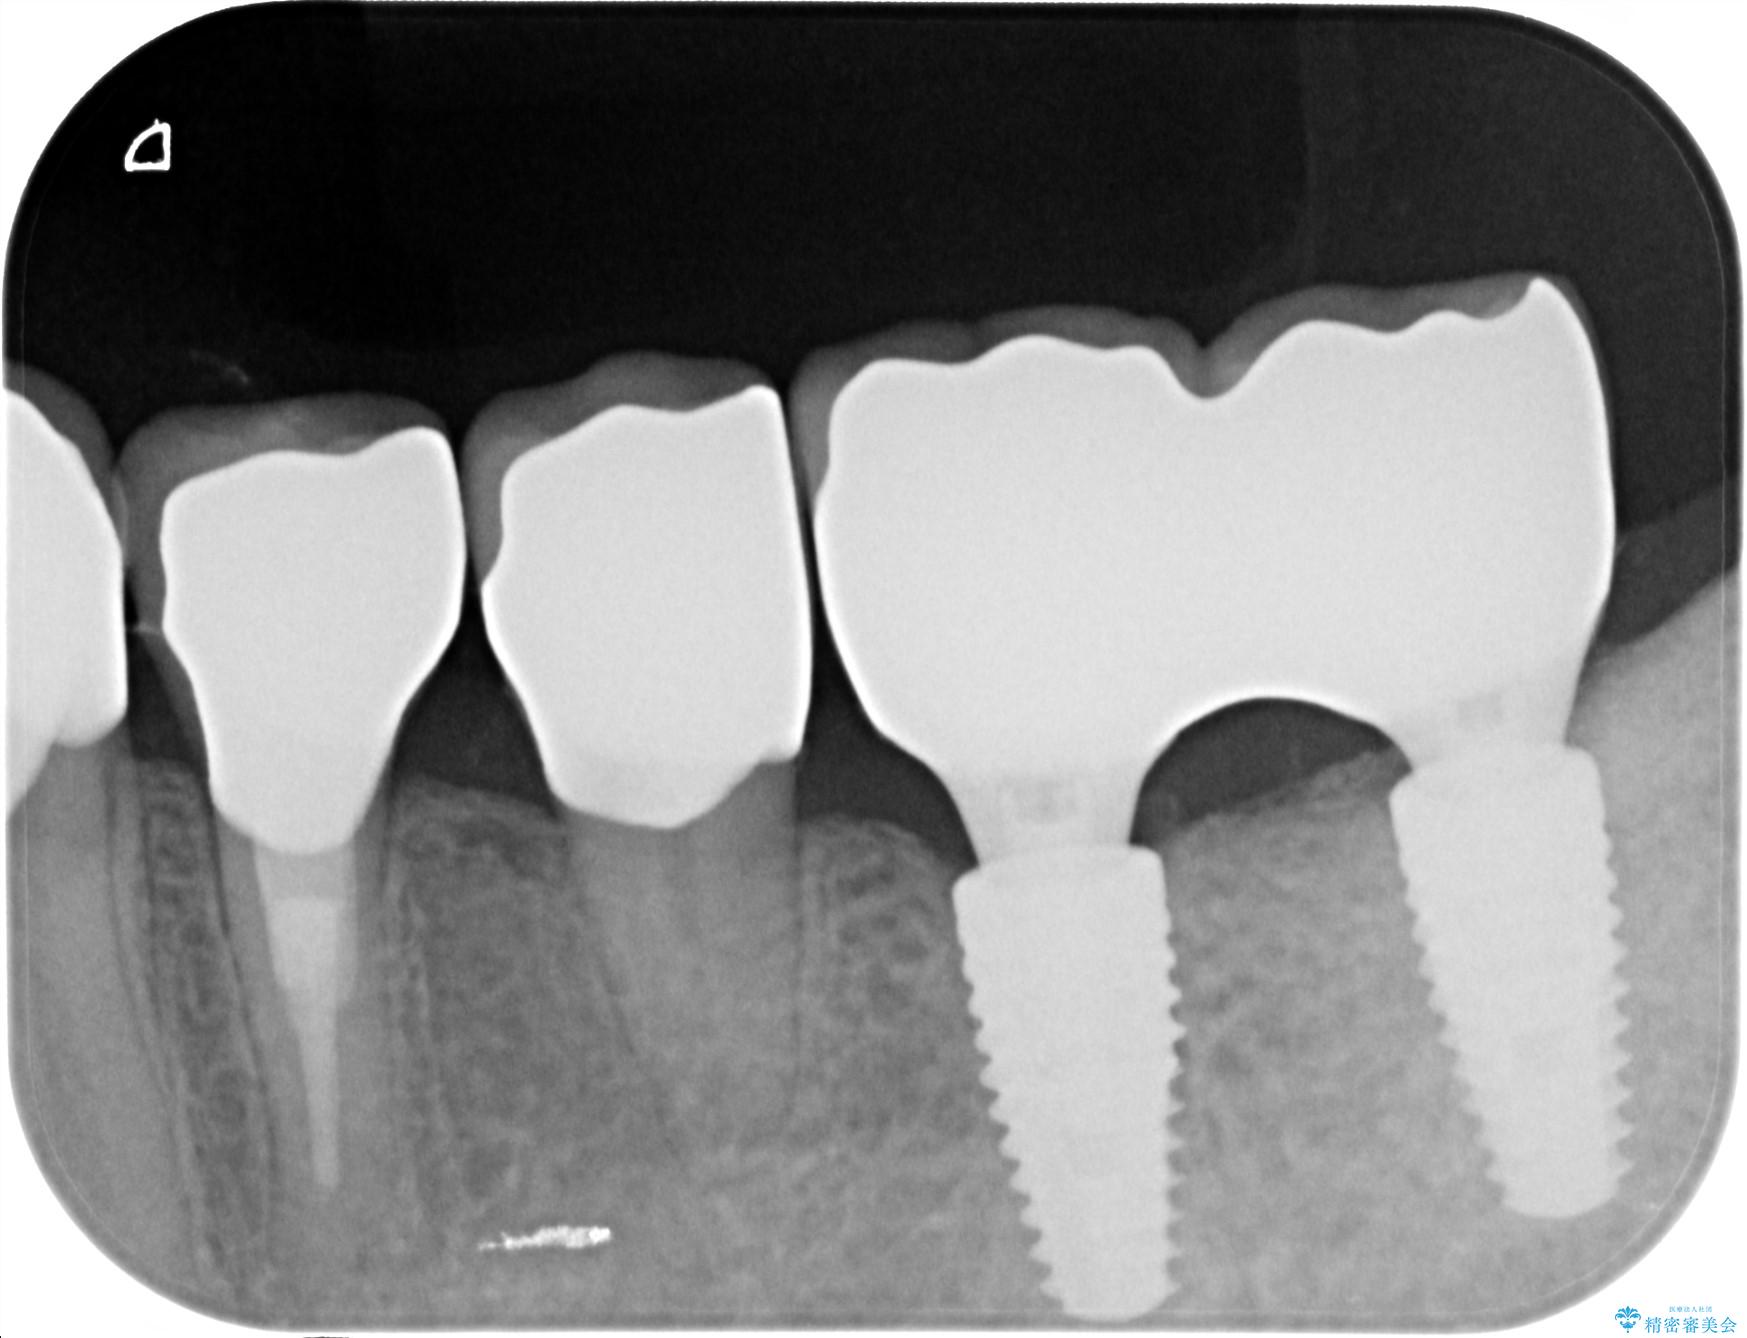

治療中

劣化の進んだブリッジの再治療[ 不適合な補綴物による虫歯の再発 ] 治療中画像 劣化の進んだブリッジの再治療[ 不適合な補綴物による虫歯の再発 ] 治療中画像 劣化の進んだブリッジの再治療[ 不適合な補綴物による虫歯の再発 ] 治療中画像

治療後

劣化の進んだブリッジの再治療[ 不適合な補綴物による虫歯の再発 ] 治療後画像 劣化の進んだブリッジの再治療[ 不適合な補綴物による虫歯の再発 ] 治療後画像 劣化の進んだブリッジの再治療[ 不適合な補綴物による虫歯の再発 ] 治療後画像